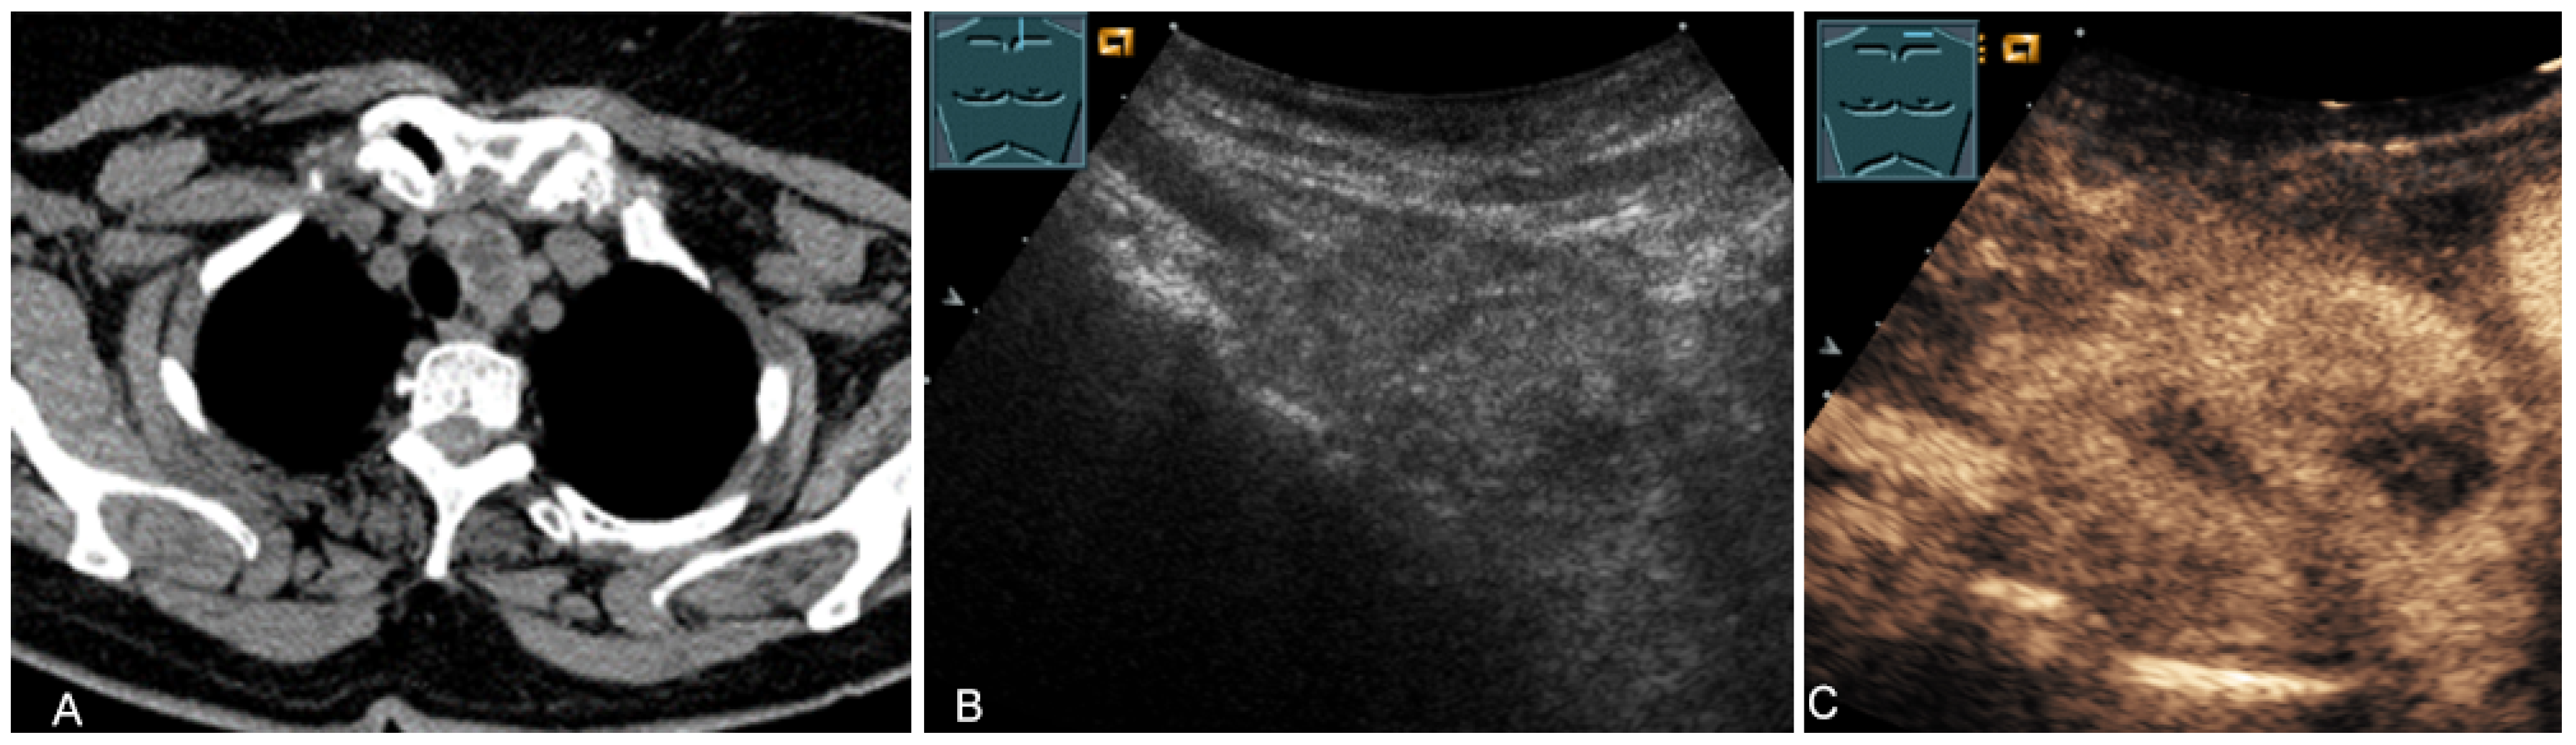

Figure 19.

A patient with tumor formation in the anterior mediastinum on CT (provided by Prof. Dr. Andreas H. Mahnken, Marburg, Germany) (A), B-mode US (B), and CEUS (C), surgically confirmed as malignant thymoma stage B1.

Figure 20.